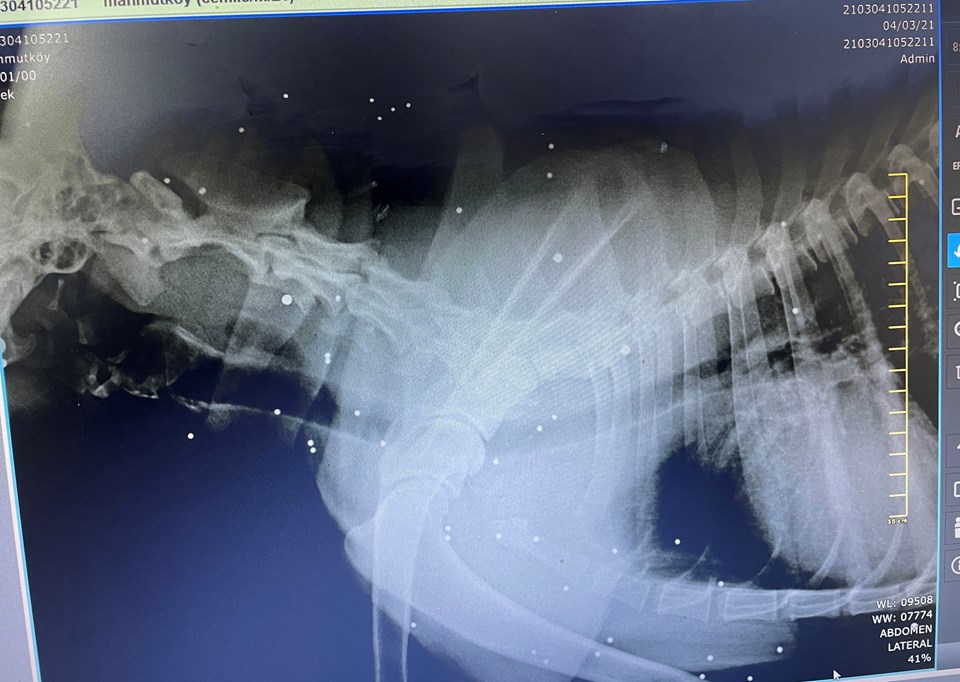

Köpeği ilçedeki bir veteriner kliniğine götürdü. Muayenesi yapılan ve röntgen filmi çekilen köpeğin, av tüfeğiyle vurulduğu ve vücudunda çok sayıda saçma olduğu ortaya çıktı. Köpekte, vücuduna saplanan saçmalar nedeniyle kurşun zehirlenmesi ve kas erimesi saptandı. Bunun üzerine Cemile Nişancı, 'Garip' adını verdiği ve elleriyle beslediği köpeği sahiplenerek evinin bahçesinde bakmaya başladı.

Cemile Nişancı, köpeğin hareketsiz halini gördüğünde üşüdüğünü düşündüğünü belirtti. Aklına köpeğin hedef tahtasına dönüştürüleceğinin hiç gelmediğini kaydeden Nişancı, "Köpek 1 hafta 10 gün sonra felç oldu. Daha sonra veteriner kliniğine getirdik. Orda yapılan kontrolde av tüfeğiyle vurulmuş olduğunu anladık. Şu an belden aşağısı tutmuyor. Elimle besliyorum. Katı besinleri çiğneyemiyor. Bu köpeği vuranlar görsün de vicdan azabı çeksin. Kafasında, çenesinde, yüzünde çok sayıda saçma var. Hedef tahtası yapmışlar. Birden fazla ateş etmişler. Gördüğümde şok oldum. Üzüntüden elim ayağım titriyor. Garip’e ölene kadar bakacağım. Bu hayvanın kimseye zararı yok. İnanamıyorum” diye konuştu.

Ke-Hayko Derneği Başkanı Sevinç Cebeci de köpeğin durumu hakkında kendilerine Cemile Nişancı’nın bilgi verdiğini ifade ederek, "Biz de alıp kliniğe getirmelerini söyledik. Üşütmeye bağlı enfeksiyonel bir durum zannettik; ama röntgen çekildiğinde gerçek ortaya çıktı. Hayvana birçok kez av tüfeğiyle ateş edilmiş. Vücudunun her yerinde saçmalar olduğunu öğrendik. Bir gözü de bu nedenle görmüyor. Rapor tutuldu. Gerekli yerlere de şikayette bulunduk. Klinikte ilaç tedavisi yapıldıktan sonra yaşı itibariyle ameliyat riskli görüldü. Gerekli mama ve tıbbi desteği vereceğiz" diyor.

Veteriner Hekim Yener Eker ise köpeğin kendilerine halsizlik, hareketsizlik ve yemek yememe şikayetiyle getirildiğini belirtti. Gerçeğin röntgenden sonra ortaya çıktığını kaydeden Yener, “Hayvanın çok acısı vardı. Kendisine dokundurtmuyordu. Vücudunda yüzlerce saçma var. Özellikle kafasında, sırtında ve akciğerlerinde. Köpeğin yaşından dolayı saçmaları operasyonla çıkartma imkanımız yok. Ağrısını kesecek uygulamalarda bulunduk. Bakımını da Cemile hanıma verdik. Bunu yapanı kınıyoruz. Umarız yapanlar bulunur" diye konuştu.